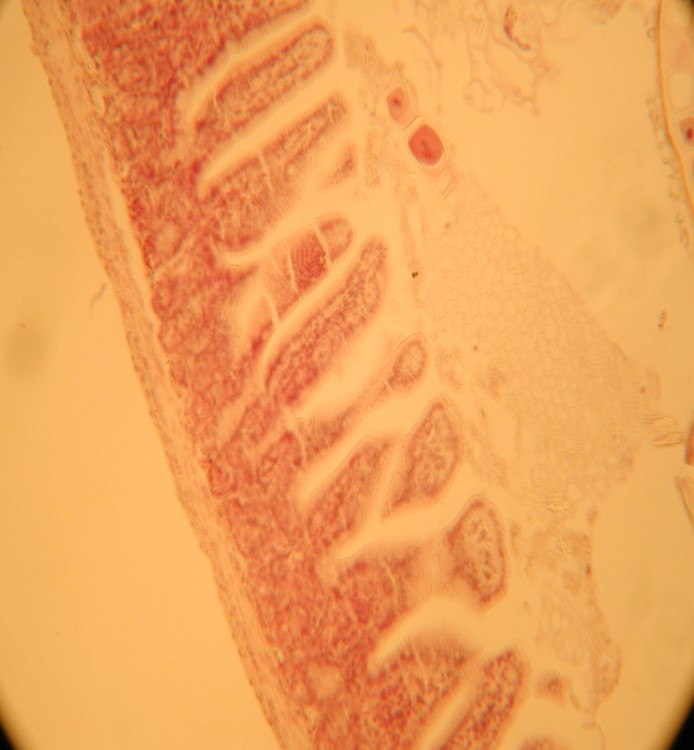

MORFOLOGIA INTESTINALE

con supplementazione

senza supplementazione